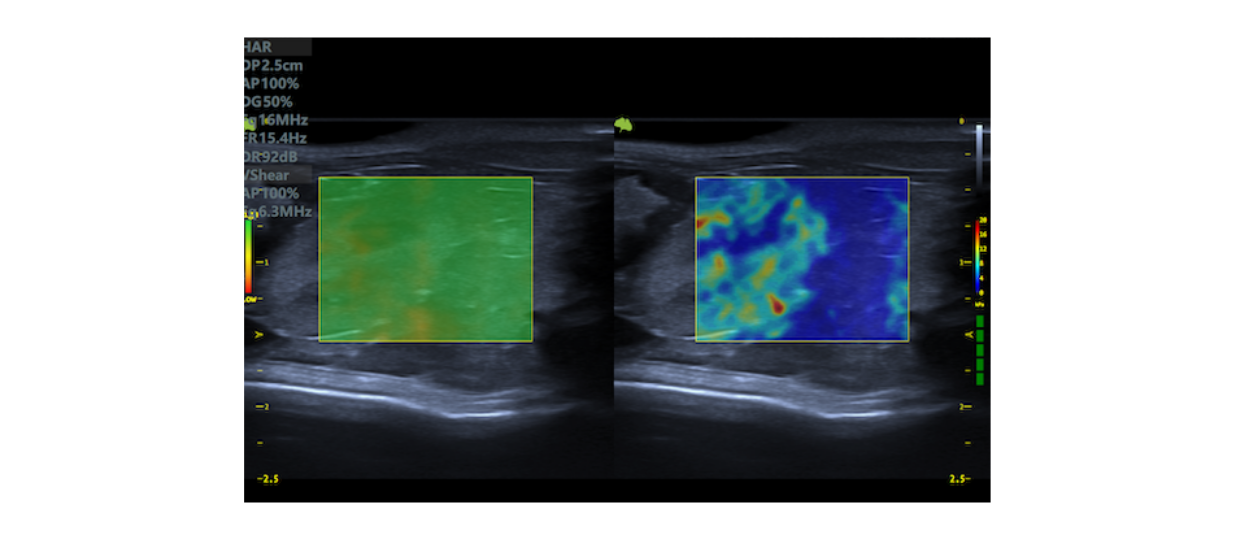

The Ultimus 9V is equipped with VINNO's revolutionary Multi-modal Ultrafast Sonography Enhanced (MUSE) platform, with the unique Tri-modal Imaging Acquisition (TIA).

Its flexibility and powerful processing allow the system intelligently apply the most appropriate imaging acquisition mode from 3 modalities to reconstruct the best imaging presentation:

Compared to traditional platforms, the MUSE platform enables higher frame rates and greater clarity, relying on a complete acoustic data processing system to dramatically increase penetration and resolution.